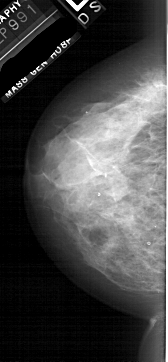

A_1877_1.RIGHT_MLO

RIGHT_MLO LINES 6061 PIXELS_PER_LINE 2461 BITS_PER_PIXEL 12 RESOLUTION 43.5 OVERLAY